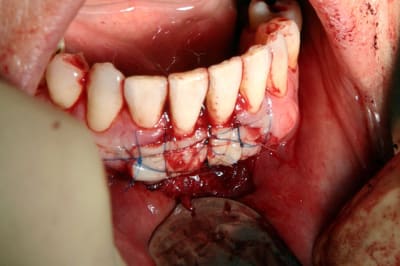

sympas tes greffes, Carole, tu places un pansement type coepack en post-opératoire?

ça dépends du temps (météo) et du feeling.....sur le cas que tu vois complet de a à z, il n' y en a pas eu, car top stabilité et uniuement de l' os en dessous

Par contre, sur la deuxième, avec les racines de 41-31, j' en ai mis....pour un max de stabilité et de protection contre les micro mouvements qui font bcp de dégat en regard des zones couvrant les racines (qui sont les plus suceptibles).Et toi?

t'utilise du fil non resorbable pour ce type de greffe ?

si, j' ai tjrs utilisé du resorbable...sauf pour cette dernière...pourquoi???? pour essayer!

verdict:

*le flop : difficile à tendre lors de la suture

*le top: hygiene, compatibilité avec coe pack, faile à deposer car glisse très bien dans les chairs.

ma conclusion: à ne pas mettre en oeuvre pour les premières fois! ;)